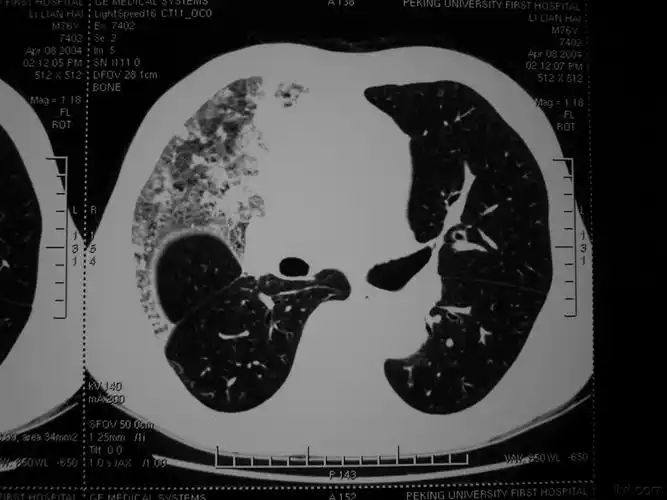

肺出血性梗死大体

1定义编辑 出血性梗死(hemorrhagic infarction)常见于肺,肠等具有

肺出血

下面这张图片主要显示的病变是 [图]a,肺出血b,肺水肿c.